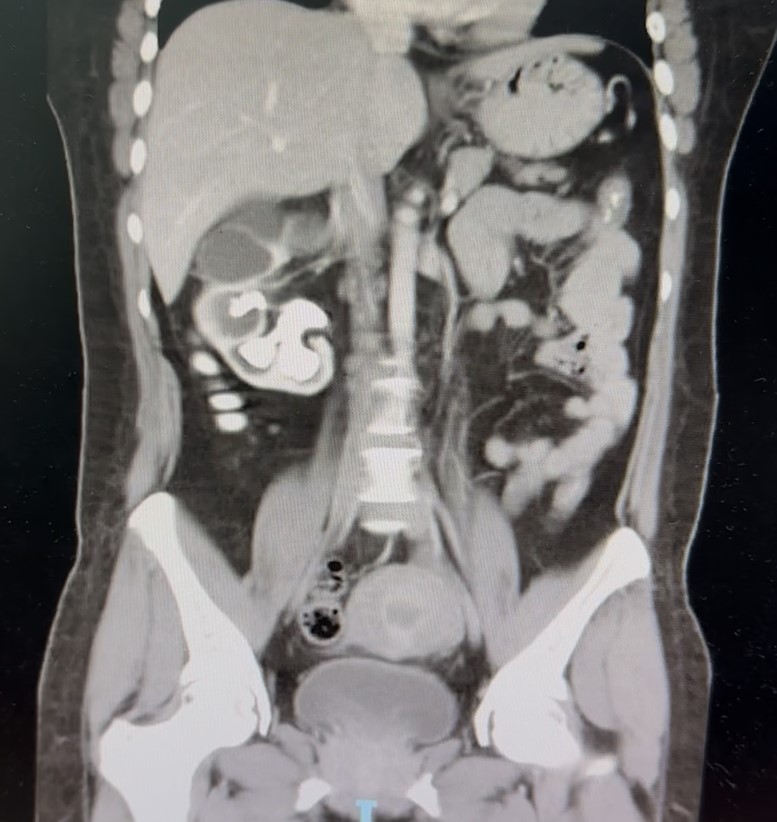

TOMOGRAFÍA COMPUTARIZADA

El hallazgo llamativo del estudio lo condiciona la presencia de hidronefrosis severa del riñón derecho (Figura 2) que se asocia a importante disminución del grosor cortical y signos de dilatación pielocalicial, que es condicionado por la presencia de una imagen hiperatenuante que ocupa completamente la pelvis y los cálices renales, adoptando una morfología ramificada (Figura 3a) y muestra densidad heterogénea mayormente hiperdensa que oscila entre los 950 y 1280 UH. El hallazgo sugiere obstrucción urinaria prolongada con probable compromiso funcional del parénquima renal (Figura 3b).

Imagen 3a: Tomografía coronal del abdomen y pelvis. Cálculo hiperdenso de gran tamaño en riñón derecho.

Imagen 3b:Riñón izquierdo presenta tamaño, morfología y grosor cortical conservados.

Figura 3a y 3b.Tomografía coronal del abdomen y pelvis. a) Cálculo hiperdenso de gran tamaño, con morfología ramificada, que ocupa por completo la pelvis renal y se extiende a los cálices mayores y menores del riñón derecho. La litiasis replica con precisión la arquitectura del sistema pielocalicial, característica de una litiasis coraliforme completa. b) En contraste, el riñón izquierdo presenta tamaño, morfología y grosor cortical conservados, sin evidencias de dilatación ni litiasis, actuando como unidad funcional compensadora. Fuente: departamento de radiología médica del Hospital Regional Dr. Rafael Hernández.